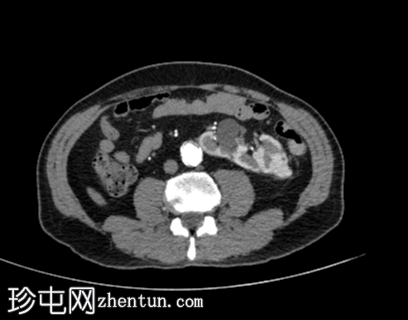

CT

轴位增强扫描

动脉期

右向左交叉融合性肾异位(轴位、冠状位和矢状位图像),右侧异位肾上极与左侧肾下极融合。

肾皮质囊肿。

主动脉-髂动脉粥样硬化晚期改变。